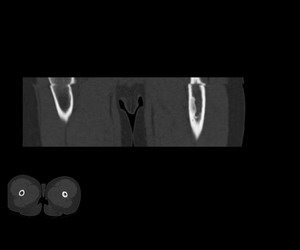

标题: PED1884:患者,男性,7岁。因右髋疼痛5天,而来院检查。 [打印本页]

标题: PED1884:患者,男性,7岁。因右髋疼痛5天,而来院检查。

因右髋疼痛5天,而来院检查。

我们考虑:1、骨皮质增厚症。2、畸形性骨炎。3、骨纤。

右髋疼痛,左侧病变,看来无症状。

支持左股骨上段骨纤维异常增殖症可能性大.